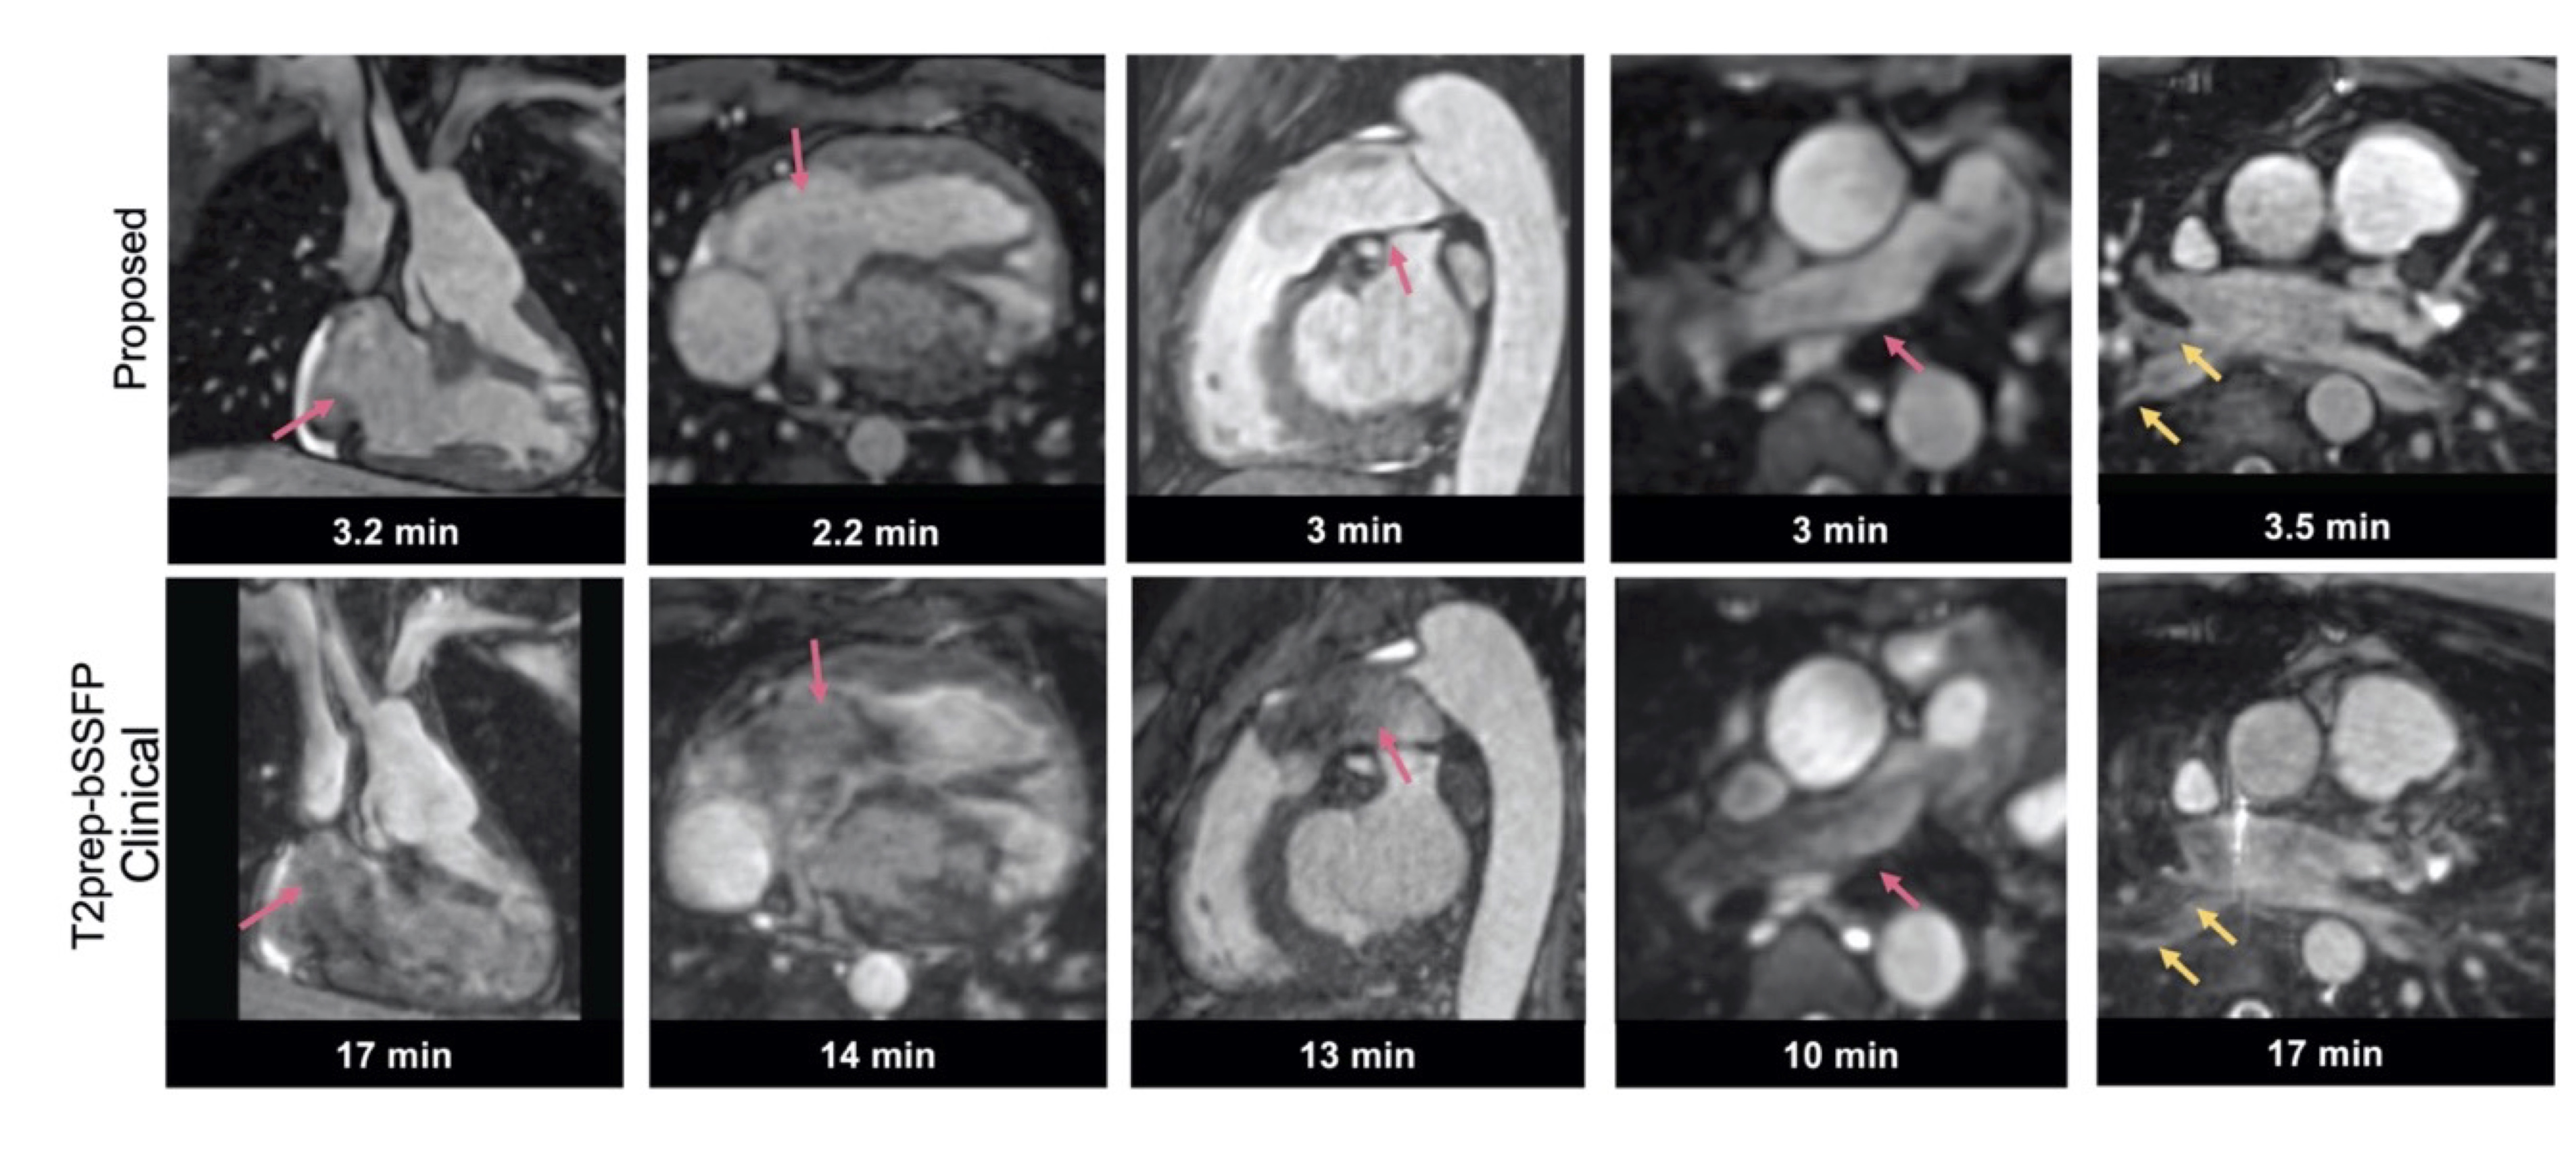

The proposed technique achieved significantly shorter acquisition time [3.2±0.7min (proposed) versus 15±3.2min (clinical), P<0.0001] (Fig. 2A). Reconstruction time for the proposed approach was 2±0.5min (inline) plus 1.5±0.5min (offline). Signal ratio comparison demonstrated comparable results with both methods for all structures, except the pulmonary veins where the proposed approach was superior (Fig. 2B). The proposed approach demonstrated a significant increase in diagnostic confidence for both reviewers [Reviewer 1: 4(3.5, 4) vs 3(2.5, 3), P=0.007; Reviewer 2: 4(4, 4) vs 4 (3, 4), P=0.009]. The overall diagnostic accuracy for the diagnosis of main and branch pulmonary artery abnormalities, aortic aneurysm/dilatation, aortic arch abnormalities, coronary artery abnormalities and anomalous pulmonary venous connections was statistically significant higher for the proposed sequence versus the clinical (0.99 vs 0.94, P<0.001) (Fig. 3). Furthermore, visual comparison of the images from both techniques demonstrated that flow and off resonance artefacts along with respiratory and non-rigid motion artefacts, were attenuated with the proposed approach (Fig. 4 & 5).

Attenuation of flow (pink arrows) and off-resonance artefacts (yellow arrows) with the proposed iNAV T2prep-bSSFP PROST sequence (first row) versus the clinical sequence (second row) in adult patients with Congenital Heart Disease.